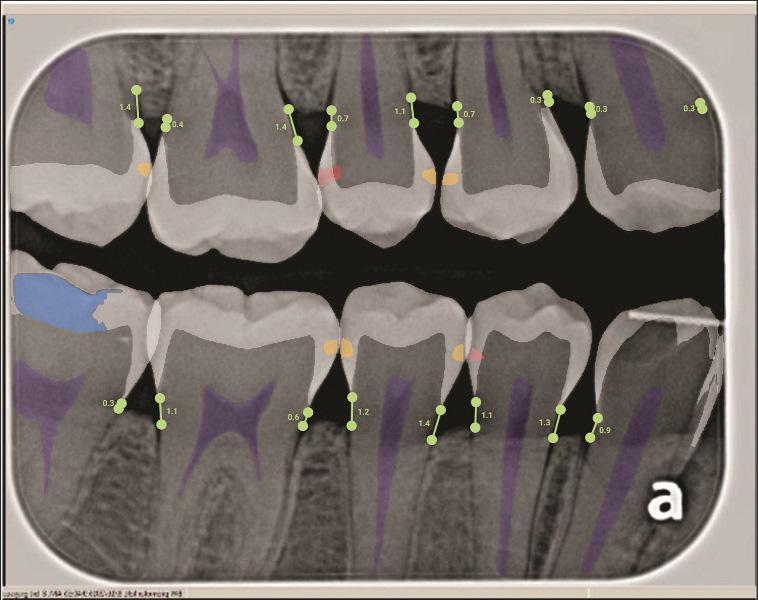

Радиационные методы диагностики кариеса (например, рентген) являются стандартом в стоматологической практике. Новшеством в радиационной диагностике является программное обеспечение на основе искусственного интеллекта (ИИ), которое может накладывать цветовые маркеры на цифровые рентгеновские снимки, указывая на участки рентгенопрозрачности, характерные для деминерализации и кариеса (Фото 4). Чувствительность (истинно положительные результаты) ИИ по сравнению с заключением экспертов составляет 73–90%, а специфичность (истинно отрицательные результаты) — 61,5–93%. Таким образом, ИИ — это лишь инструмент, помогающий стоматологу выявить потенциальные поражения. Анализ ИИ наиболее полезен для повышения чувствительности при выявлении кариеса эмали. Исследование показало, что использование ИИ для диагностики кариеса эмали увеличивает применение профилактических методов, но также повышает частоту инвазивного лечения.

Фото 4: Обнаружение кариеса с помощью искусственного интеллекта (ИИ), демонстрирующее несколько начальных поражений эмали.